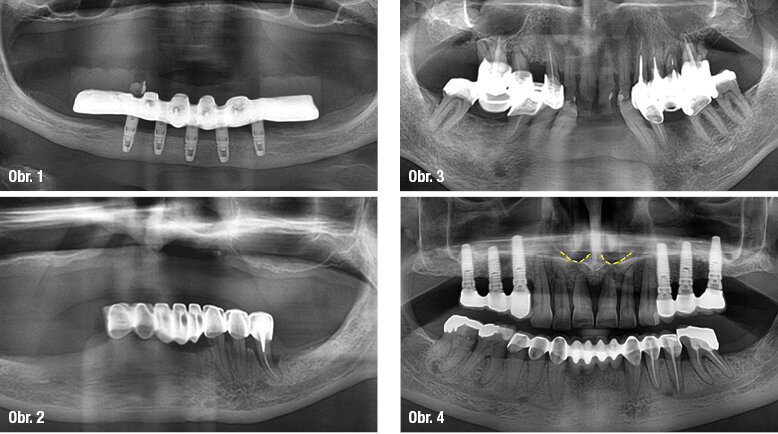

Kost v této krajině, zvláště je-li atrofovaná, je téměř vždy kvalitní. I při výrazné resorpci je jí dostatek pro zakotvení Brånemarkova můstku. Dokonce lze implantovat i při kompletní resorpci alveolárního výběžku a persistenci pouze bazální části mandibuly (obr. 1).

Souhrn: Riziko nadměrné resorpce kosti v této krajině není velké, téměř vždy se můžeme obejít bez augmentace. Přílišná obava z negativního efektu prolongované parodontologické terapie tedy není na místě.

Při pokročilé resorpci laterální části alveolárního výběžku mandibuly dochází často po ztrátě zubů a zhojení extrakčních ran k situaci, kdy šroubové a v horších případech i čepelkové implantáty nejsou použitelné. Limitující anatomickou strukturou je mandibulární kanál. Augmentační procedury jsou v uvedených místech obtížné. Avšak vzhledem k tomu, že u Brånemarkova můstku není do této krajiny implantováno, nehraje resorpce kosti z praktického hlediska roli (obr. 2).

Souhrn: Resorpce kosti způsobená parodontitidou v této lokalitě implantologa neomezí.